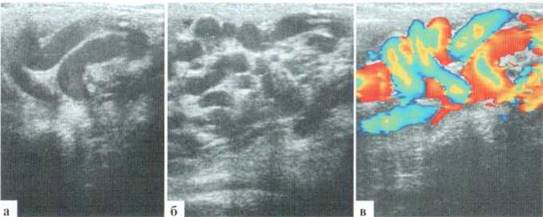

Проводится проба Вальсальвы: датчик устанавливается слева у корня мошонки, включается режим цветового доплера. По просьбе врача подросток последовательно делает глубокий вдох и затем напрягает живот, в течение этого времени оценивается сосудистый рисунок в проекции гроздьевидного сплетения (рис. 3.4). При подозрении на варикоцеле справа проба повторяется справа. При положительной пробе Вальсальвы уже на вдохе определяются реверс кровотока и значительное усиление сосудистого рисунка, которое достигает максимума во время напряжения передней брюшной стенки.

Рис. 3.4. Проба Вальсальвы:

а — исходное состояния; б — глубокий вдох — смена направления кровотока (стрелка); в — напряжение передней брюшной стенки резкое нарастание интенсивности окрашивания сосудов соответственно увеличению скорости кровотока